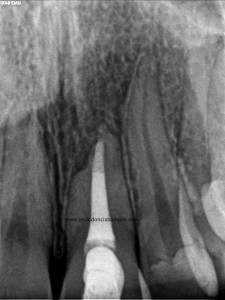

La paciente fue llamada a revisión al año:

Y más tarde, a los dos años:

Esta paciente nos llegaba sin sintomatología, y la lesión ha regenerado correctamente, con lo que podemos decir que hemos tenido éxito en el tratamiento.